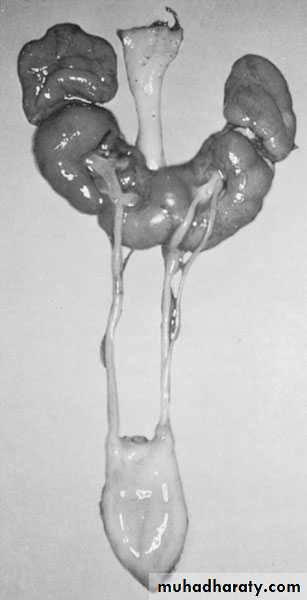

Horseshoe Kidney

found in 1:1000 necropsies an is commoner in men.

probably the most common of all renal fusion anomalies

The anomaly consists of two distinct renal masses lying

vertically on either side of the midline and connected at

their respective lower poles by a parenchymatous or fibrous

isthmus that crosses the midplane of the body.

Fusion of the renal masses early in embryonic life, so its ascent

will be impeded by inferior mesenteric artery.

The kidneys are low located, mal rotated and pelves lie anteriorly

Symptom When present, they are related to complications like hydronephrosis, infection, or calculus formation

Diagnosis ultrasound, IVU, CT scan